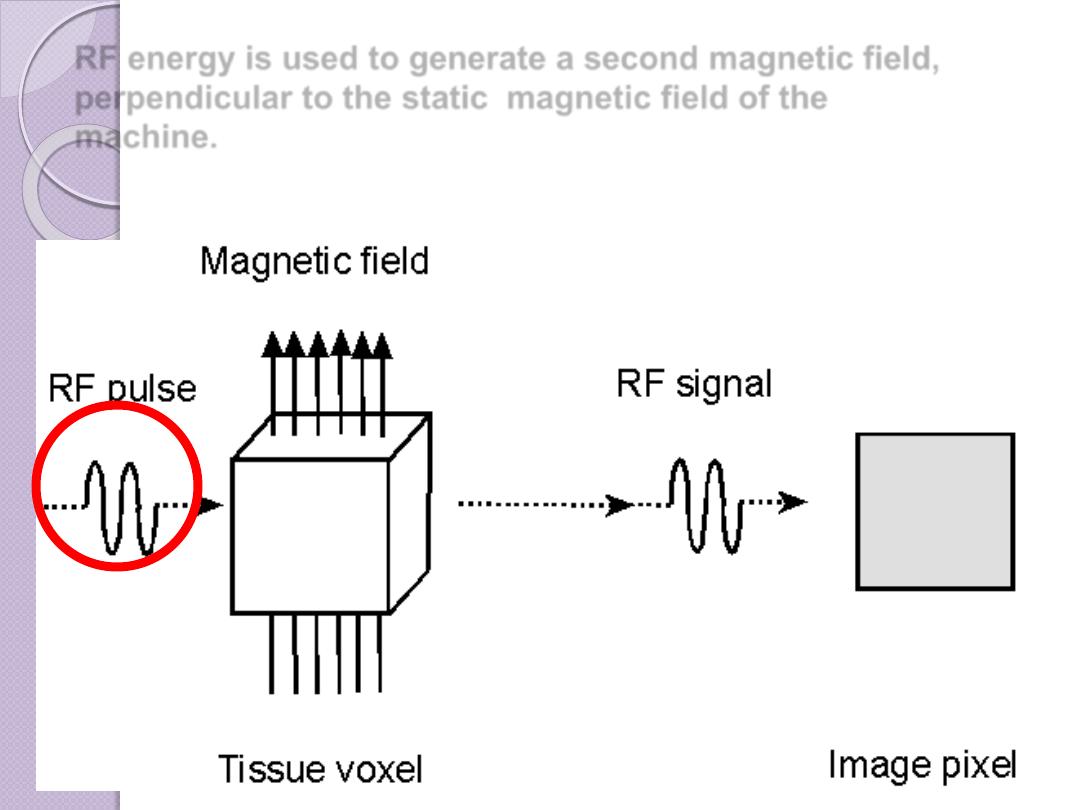

Magnetic resonance imaging (MRI) combines a strong

magnetic field

and

radiofrequency

(RF) energy to study the distribution and behaviour of hydrogen protons

in fat and water

RF energy is used to generate a second magnetic field,

perpendicular to the static magnetic field of the

machine.

The result of this second

magnetic field is to rotate or

flip the protons away from the

static magnetic